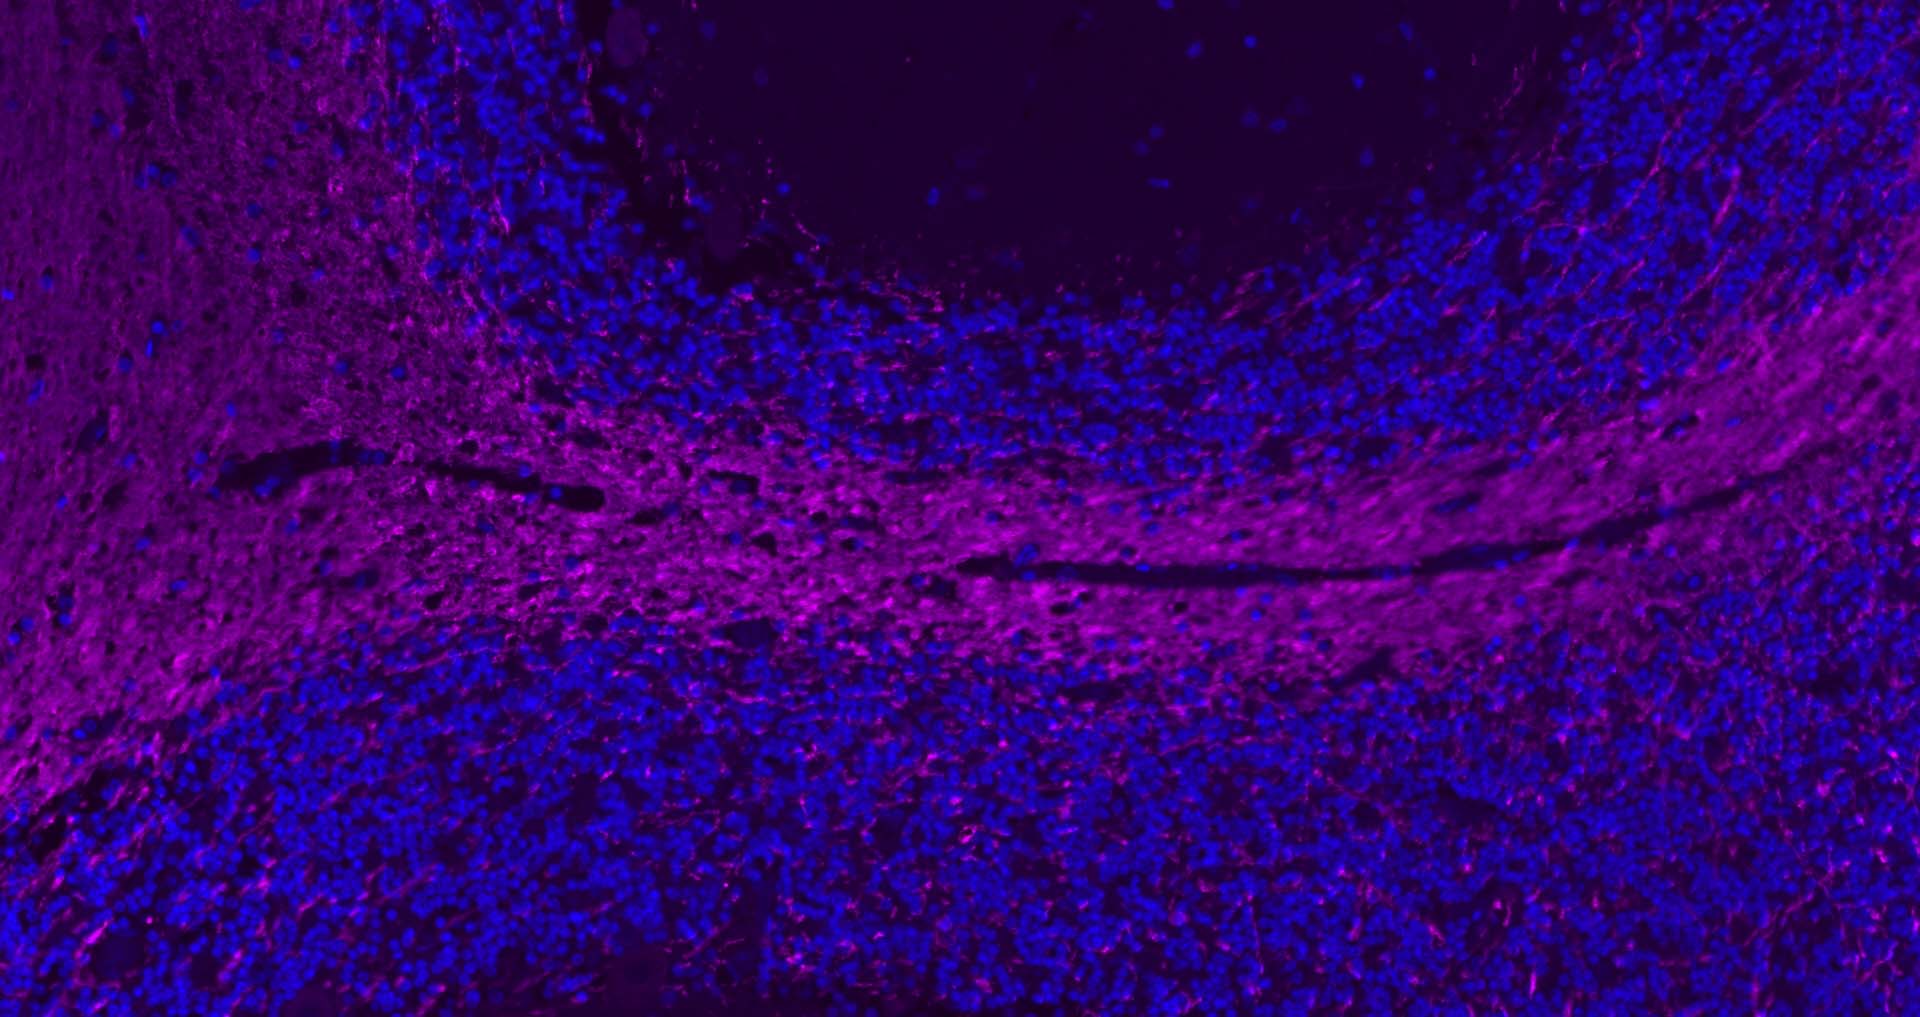

| 背景资料 | Oligodendrocyte Marker The classic group of Myelin basic protein (MBP) isoforms (isoforms 4 to 14) are with PLP the most abundant protein components of the myelin membrane in the CNS. They have a role in both its formation and stabilization. The smaller isoforms might have an important role in remyelination of denuded axons in multiple sclerosis. The non classic group of MBP isoforms (isoforms 1 to 3/Golli MBPs) may preferentially have a role in the early developing brain long before myelination, maybe as components of transcriptional complexes, and may also be involved in signaling pathways in T cells and neural cells. Differential splicing events combined to optional posttranslational modifications give a wide spectrum of isomers, each of them having maybe a specialized function. |

| {IHC-P} | {1:500-2000} |

| {IHC-F} | {1:500-2000} |

文献和实验[IF={{ 8.352 }}] {Chanjuan Dong. et al. Graphene-based conductive fibrous scaffold boosts sciatic nerve regeneration and functional recovery upon electrical stimulation. Appl Mater Today. 2020 Dec;21:100870} {IHC} {Rat}

[IF={{ 7.4 }}] {Ruoyan Xue. et al. Mesenchymal Stem Cell-Derived Exosomes Promote Recovery of The Facial Nerve Injury through Regulating Macrophage M1 and M2 Polarization by Targeting the P38 MAPK/NF-Κb Pathway. AGING DIS. 2024 Apr 1; 15(2): 851–868} {IF} {Rat}